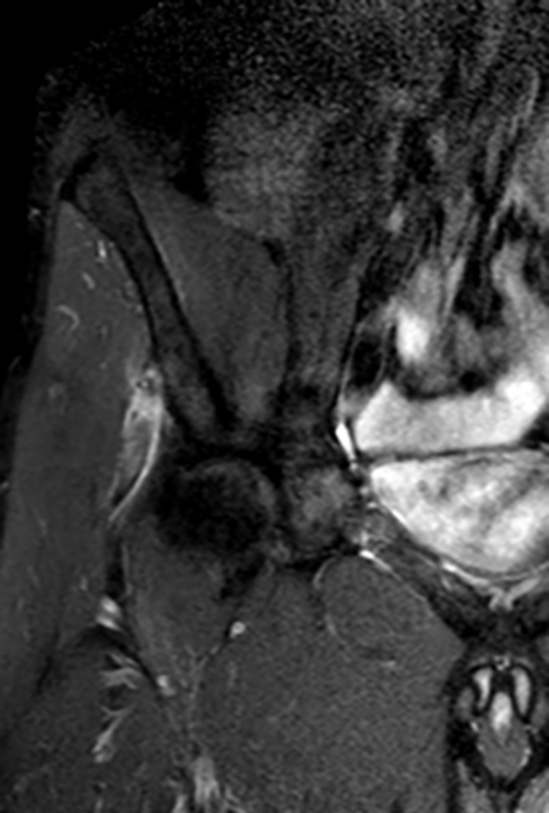

Rectus femoris-Verletzungen werden anhand einer klinischen Untersuchung und mit Hilfe von Röntgenbildern diagnostiziert. Dabei fallen oft ein Hämatom (Bluterguss) und Schmerzen am anterioren (vorderen) Beckenbereich (Spina iliaca anterior superior) und in der Leiste auf. Die Kraft bei der Kniebeugung kann reduziert sein und die Bewegung löst typischerweise Schmerzen aus. Im Röntgenbild könnte ein knöcherner Ausriss ersichtlich sein. Eine MRI-Untersuchung ist für die Diagnose nicht entscheidend, kann aber bei schweren Symptomen wichtige Informationen über das Verletzungsausmass geben (Retraktion, Grösse der Ruptur).

Links ein Röntgenbild und rechts eine MRI-Aufnahme der rechten Hüfte mit knöchernem Ausriss des proximalen Musculus rectus femoris.

Bilder: Universitätsklinik Balgrist